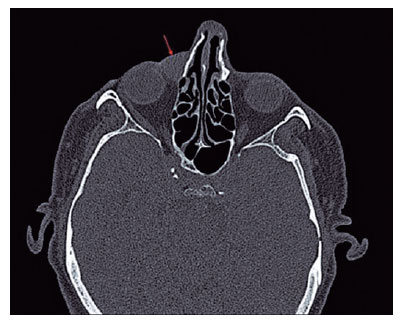

A 65-year-old male complained of epiphora and swelling in the right medial canthal region for approximately 3 months. After reviewing the patient’s medical records, a mass was recorded three months ago, but the lacrimal irrigation was patent. The patient did not undergo further examination. During the examination, a semimotile, nontender mass, measuring approximately 10 × 15 mm, was detected. Diagnostic lacrimal irrigation tests revealed a hard stop an obstruction. The patient’s best-corrected visual acuity was 20/20 in both eyes and the anterior and posterior segments were normal based on biomicroscopic examination. Orbital computed tomography (CT) revealed a well-circumscribed hypodense soft tissue mass in the right medial orbit (18 × 11 mm) that did not spread to the surrounding tissues (Figure 1).